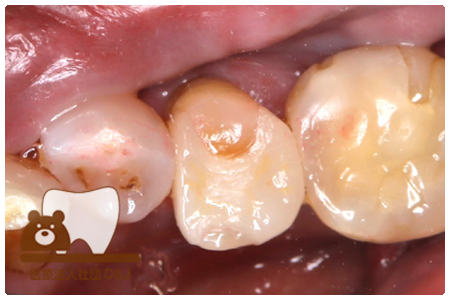

症例8フルジルコニアクラウン

治療前

治療中

治療後

29歳 女性

- 治療内容

- 銀歯からフルジルコニアクラウンへの修復

- 治療期間

- 根の治療含め3か月

- 費用

- 自費

フルジルコニアクラウン:77,000円(税込)

- その他の治療の費用は含まれておりません。

- リスク・副作用

- 強い衝撃が加わると欠けたり割れたりする可能性があります。また、噛み合わせの状態によっては脱離や周囲の歯への影響が出ることもあります。